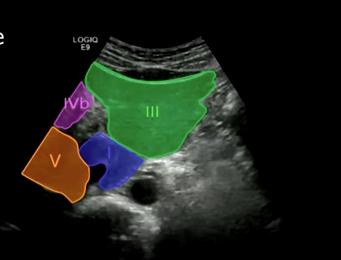

Middle finger: Segments four a and four b.

Middle hepatic vein separates segments: superior (four a and eight), inferior (four b and five). It serves as an important surgical landmark.

Gallbladder: Segment four. The gallbladder is located in the gallbladder fossa of segment four.

Inferior segments (close to transducer): Segments three and four b.